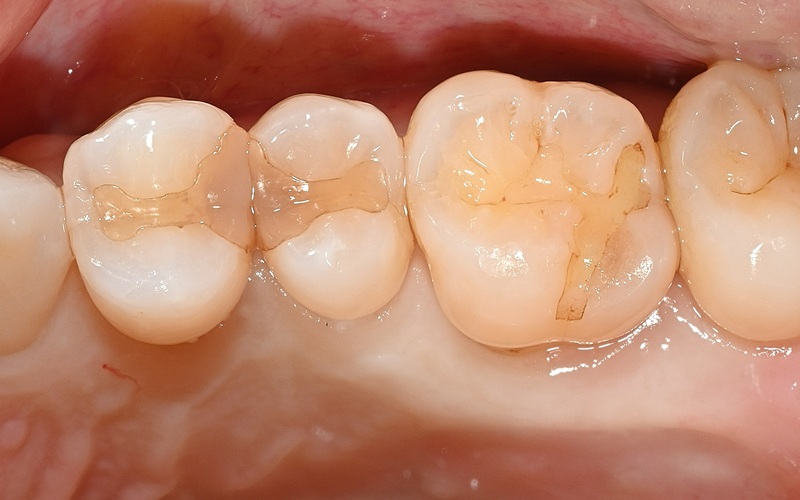

Case2

術前

ラバーダム防湿

術後

| 治療名 | ダイレクトボンディング |

|---|---|

| 治療説明 | 虫歯が発生したため、ダイレクトボンディングを行いました。ラバーダムを装着し、う蝕を除去してレジンを充填し、見た目と機能を回復しました。 |

| 治療回数・期間 | 1回 |

| 副作用とリスク | 知覚過敏症状が生じる恐れがあります。レジンが破折歯修復が必要となることがあります。 |

| 料金(税込) | 55,000円(自費) |